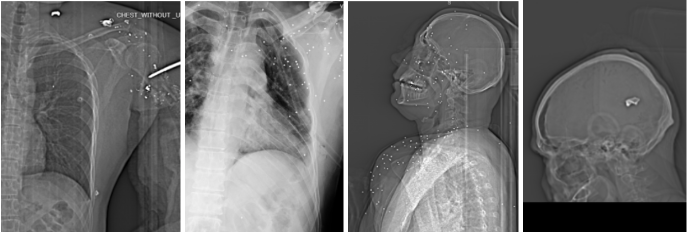

با این حال، پزشکانی که این تصاویر را دیدهاند در ارزیابیهای متعدد از اصطلاحات بالینی صریح برای توصیف سطح خطر استفاده کردهاند، از جمله «خطر بسیار بالای مرگ»، «خونریزی تهدیدکننده حیات»، «آسیب فاجعهبار»، «احتمال آسیب عروقی عمده»، و «خطر سکته ویرانگر»، همچنین یافتههایی مانند هموپنوموتوراکس شدید یا نیاز به درمان فوری و تهاجمی. در یک مورد، وجود پانسمان هموستاتیک از نوع Quick Clot بهطور مشخص بهعنوان یافتهای سازگار با خونریزی بسیار شدید و خطر مرگ ظرف چند دقیقه در صورت کنترلنشدن سریع ذکر شده است.

وجود لوله قفسه سینه در چند تصویر، بهعنوان نشانه مداخله اورژانسی برای پنوموتوراکس یا خون و هوا در فضای جنب، بهطور مستقیم شدت آسیب قفسه سینه و خطر آن را برجسته میکند. در بعضی موردها، لولهگذاری تنفسی و نیز گاز زیاد در معده بهعنوان قرینهای محتمل از احیای تنفسی یا اقدامات حمایتی پیشرفته ذکر شده است. همچنین گاز زیر پوست یا گاز در بافت نرم در چند آسیب نافذ، بهعنوان نشانه جراحت باز یا نافذ و همخوان با تروماهای ناشی از گلوله یا نفوذی توضیح داده شده است. این شاخصها، بهویژه وقتی کنار هم مینشینند، تصویر روشنتری از شدت تروما و سطح بحران پزشکی ارائه میدهند.

در یک مورد، پزشک به جابجایی نای و افزایش دانسیته و پهنشدگی نامتقارن بافت گردن اشاره کرده و آن را با خونریزی و تورم سازگار دانسته است. در همان چارچوب، احتمال آسیب به عروق بزرگ گردن و پیامدهایی مانند مرگ یا سکته ویرانگر مطرح شده است. همچنین در مواردی که شکستگیهای نزدیک شانه یا گردن همراه با قطعات فلزی دیده میشود، پزشک بهصورت احتیاطآمیز از خطر آسیب عروق و اعصاب گردن و «ریسک سکته» سخن میگوید.

در چند پرونده قفسه سینه، ترکیبی از یافتهها تکرار میشود: زخم باز یا نافذ، گاز زیر پوست، آسیب ریه، و لوله قفسه سینه. پزشکان توضیح دادهاند که پنوموتوراکس میتواند با پر شدن فضای اطراف ریه از هوا، ریه و حتی قلب را تحت فشار قرار دهد و بدون درمان، کشنده باشد.

مقایسه الگوهای آسیب تهدیدکننده حیات در قفسه سینه شامل گلوله ۳۹×۷٫۶۲ با پنوموتوراکس و لوله قفسه سینه، اسلاگ ۱۲ گیج با تخریب متمرکز، و شاتگان نزدیکبرد با هموپنوموتوراکس شدید.

در برخی موردها، همزمان از خونریزی در فضای اطراف ریه یا هموتوراکس نیز یاد شده که آن هم میتواند پرریسک باشد. در یک مورد، امکان عبور پرتابه از یک سمت قفسه سینه به سمت دیگر و در نتیجه احتمال آسیب به اندامهای دیگر نیز بهصورت شرطی مطرح شده است؛ یعنی وابسته به اینکه محل زخم ورودی کجا بوده است.

از نظر الگوی آسیب، شکستگیهای خردشونده در استخوانهای ران، لگن و بازو بهطور تکرارشونده مشاهده شدهاند. در چند مورد، آسیب قفسه سینه با پنوموتوراکس (هواجنبی) و نیاز به مداخله اورژانسی همراه بوده است. در یک پرونده، گلوله در ناحیه گردن دیده شده و با جابجایی نای و نشانههای تورم و خونریزی سازگار بوده است؛ وضعیتی که پزشک آن را با احتمال آسیب به عروق بزرگ و خطر سکته یا مرگ مرتبط دانسته است. در یک مورد دیگر، درگیری مغزی با ریسک بسیار بالای مرگ توصیف شده است. همچنین در چند مورد، احتمال آسیب به شریان فمورال (سرخرنگ رانی) و خطر خونریزی تهدیدکننده حیات مطرح شده است.